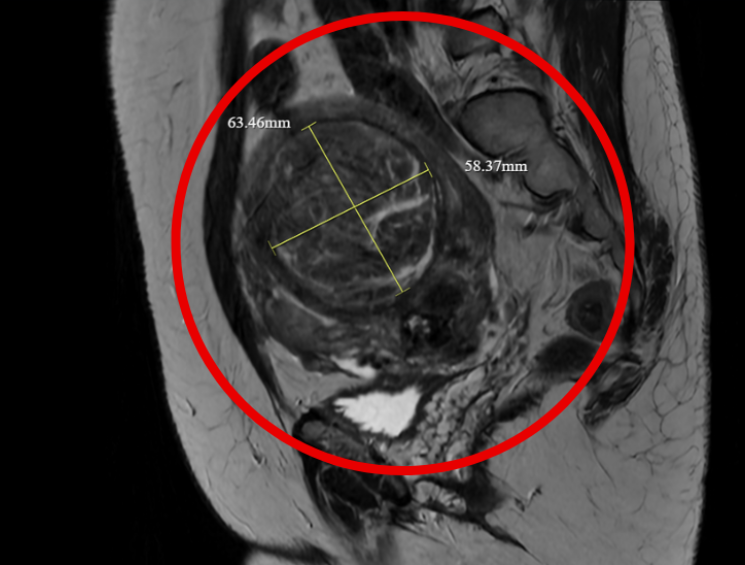

Hình ảnh siêu âm và chụp cộng hưởng từ cho thấy các khối u xơ chèn ép vào nhiều cơ quan, đặc biệt là bàng quang và trực tràng dẫn đến tình trạng căng tức khó chịu", ThS.BS Đỗ Huy Hoàng, Khoa Chẩn đoán hình ảnh và Điện quang can thiệp, Bệnh viện Đa khoa Hồng Ngọc - Phúc Trường Minh cho hay.

Hình ảnh siêu âm cho thấy nhiều u xơ tử cung, trong đó khối lớn nhất gần 7cm - Ảnh BVCC

Hình ảnh khối u trước và sau khi nút mạch, toàn bộ mạch máu được nút tắc thành công - Ảnh BVCC